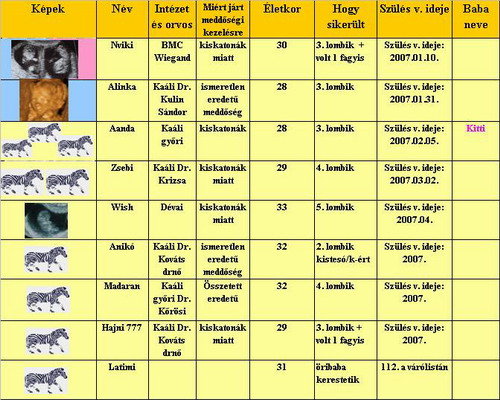

Zsebi! A táblába is bekerülhetnék? (Bár most jön a kettes számú para a méhnyak állapota miatt...)